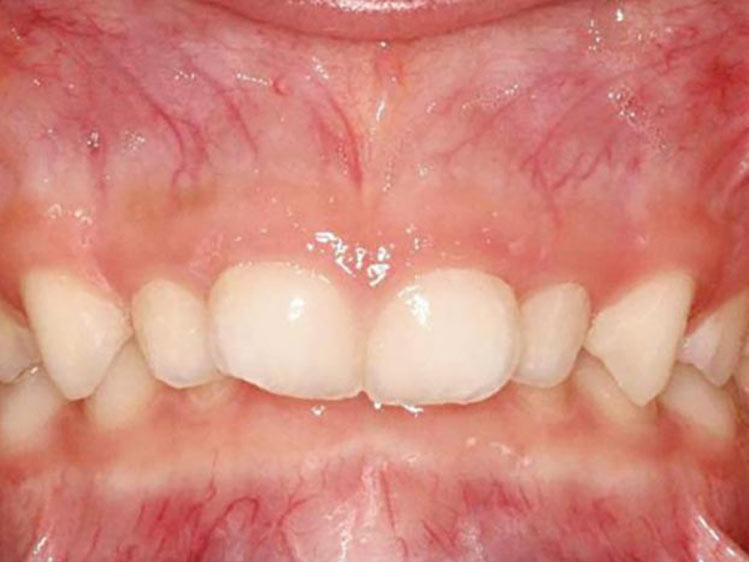

É necessário fazer uma avaliação clínica e radiográfica criteriosa da oclusão do paciente.

A primeira consulta a um ortodontista infantil deve ocorrer por volta dos 5/6 anos de idade, período que antecede as trocas dentárias.

Nesse momento tão dinâmico da vida dos pequenos é importante acompanhar de perto as transformações, se certificando se estas mudanças estão acontecendo de forma correta.

Se algo estiver fora da normalidade, o problema poderá ser interceptado e corrigido prontamente, evitando longos tratamentos ortodônticos no futuro.